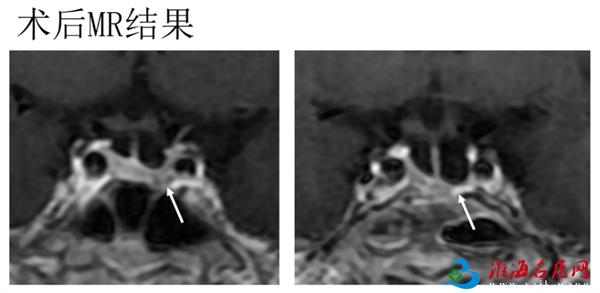

手术当天,殷杰副主任医师在神经内镜的帮助下,通过术前影像学定位及术中患者的蝶窦解剖情况,确定了肿瘤隐藏的位置,全切了肿瘤。

手术全程通过鼻腔作为通道,头面部没有手术切口,出血仅100ml。术后复查,影像显示肿瘤切除完全。